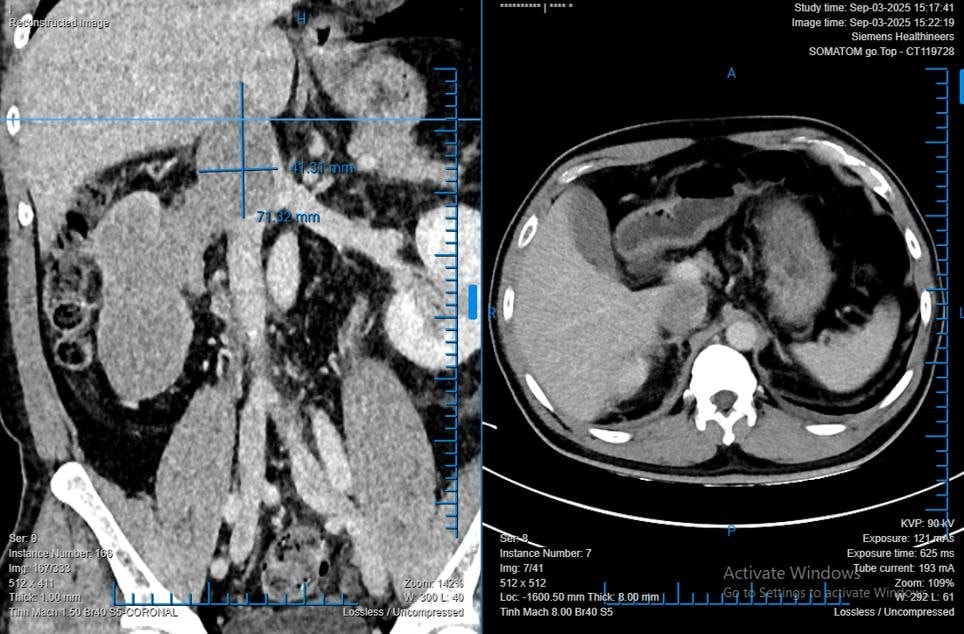

Anh T.D.L (48 tuổi, quê Quảng Trị), phát hiện bướu thận tình cờ trong lần khám sức khỏe định kỳ. Được các bác sĩ địa phương giới thiệu, anh tìm đến Bệnh viện Bình Dân để phẫu thuật. Qua chẩn đoán hình ảnh, khối bướu chiếm gần toàn bộ thận phải, có kích thước 68 x 86 x 138 mm; huyết khối bướu lan sâu vào tĩnh mạch thận và tĩnh mạch chủ dưới. Bệnh nhân có nguy cơ tử vong, nếu không được can thiệp kịp thời.

Ca mổ kéo dài 8 giờ liên tục với sự phối hợp của 4 ê-kíp bác sĩ chuyên khoa tiết niệu, gan mật, tim – mạch máu và gây mê hồi sức. Các bác sĩ lần lượt di động gan, bộc lộ tĩnh mạch chủ đoạn sau gan, cắt bỏ toàn bộ thận phải cùng huyết khối bướu trong tĩnh mạch. Khác với phương pháp truyền thống cần phối hợp mổ mở để lấy huyết khối bướu, ca mổ của anh L. đã được thực hiện hoàn toàn bằng phẫu thuật robot.

TS.BS. Phạm Phú Phát – Trưởng Khoa Niệu A, Bệnh viện Bình Dân – chia sẻ: “Đây là trường hợp ung thư biểu mô tế bào thận (RCC) có huyết khối bướu lên đến 76 mm, lớn nhất trong số các trường hợp mà tôi từng phẫu thuật. Một báo cáo tại Hoa Kỳ cũng ghi nhận chiều dài huyết khối bướu lớn nhất là hơn 70 mm. Với kinh nghiệm phẫu thuật robot và sự phối hợp đa chuyên ngành, chúng tôi đã lấy huyết khối bướu hoàn toàn bằng phẫu thuật robot.”